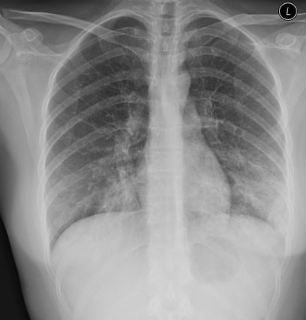

¿Qué nos permite ver la radiografía?

A

• Columna de aire tráquea

• Ángulos borrados

• Consolidaciones o patrón intersticial